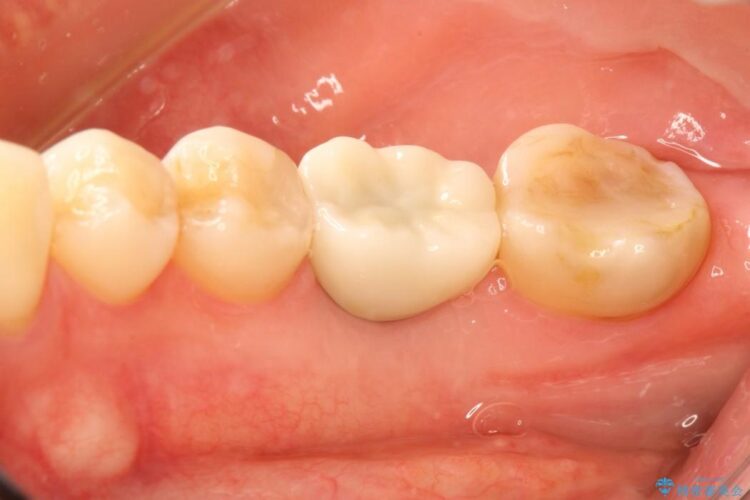

抜歯を行った当日に骨の維持をする為、人工の骨を充填しました。インプラントを埋入する際には、ほとんどが自分の骨に置き換わっており、頬舌的なへこみを引き起こす事もなく、審美性・機能性ともに維持する事が出来ました。

また今回の治療では「バイコンインプラント」を使用する事により、インプラントの土台とセラミッククラウンを付ける際にセメントが全く残らないという利点を生かしたところ、見た目にも綺麗に仕上がり、患者様にも喜んでいただきました。

※下あごのインプラント治療の場合、ネジで止めるインプラントでは「ネジ止め用の穴」が少し見えてしまい審美性に欠けるデメリットがあります